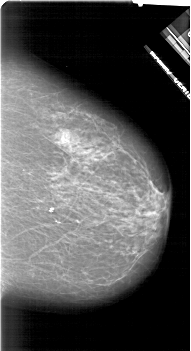

A_1628_1.RIGHT_MLO

RIGHT_CC LINES 6316 PIXELS_PER_LINE 3421 BITS_PER_PIXEL 12 RESOLUTION 43.5 NON_OVERLAY

RIGHT_MLO LINES 6361 PIXELS_PER_LINE 3871 BITS_PER_PIXEL 12 RESOLUTION 43.5 NON_OVERLAY